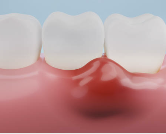

✅ 5. 잇몸이 들뜨거나 약간 들린 느낌

잇몸과 치아가 밀착되어 있어야 하는데

치은염이 있으면 잇몸이 벌어지면서 약간 들뜬 느낌이 들어요.

심해지면 음식물이 잇몸 속으로 들어가

잇몸 통증이나 염증 악화로 이어질 수 있습니다.